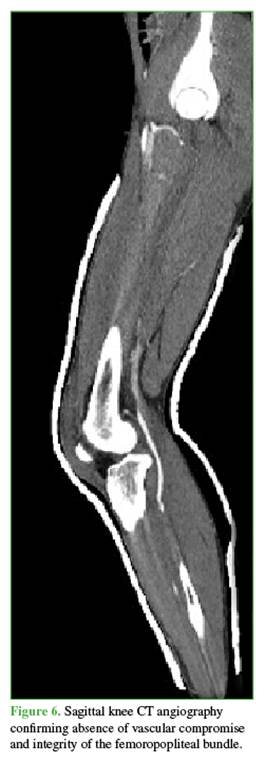

Radiographs showed widening of the medial joint space consistent with medial instability. Further imaging was obtained with magnetic resonance imaging (Figures 4 and 5) to evaluate possible interposed tissues or structures, and with CT angiography (Figure 6) to rule out vascular injury given the time elapsed since trauma. Marked edema was noted in the medial soft tissues, including the capsule and medial structures in the intercondylar region, along with persistent knee subluxation. Vascular compromise was ruled out, with preservation of the femoropopliteal vascular bundle.